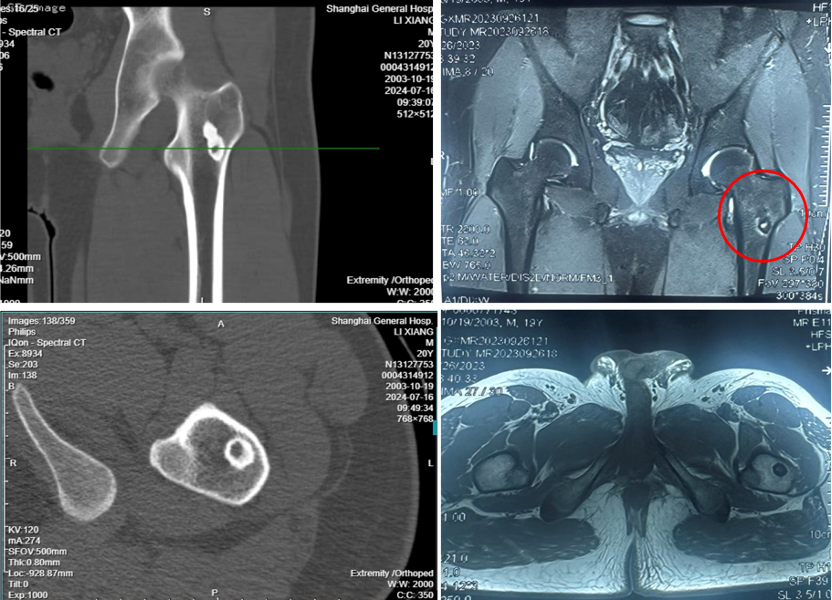

图2:术前CT及MRI见髓腔内松质骨内的瘤巢及周围明显的成骨反应,MRI水肿反应不如骨膜及皮质骨型明显

入院后诊断为中心型股骨髓腔骨样骨瘤,本型临床症状不如皮质型明显,部分患者疼痛隐匿,单纯射频消融效果较好。入院后第二天全身麻醉后导航下行左侧股骨病灶射频消融术,选择消融针尺寸为15毫米,消融时间11分30秒。术后第二天患者自诉原有疼痛不适症状缓解90%。术后复查MRI可见骨内明显的椭圆形消融范围,精准对应了23*19毫米的消融范围。